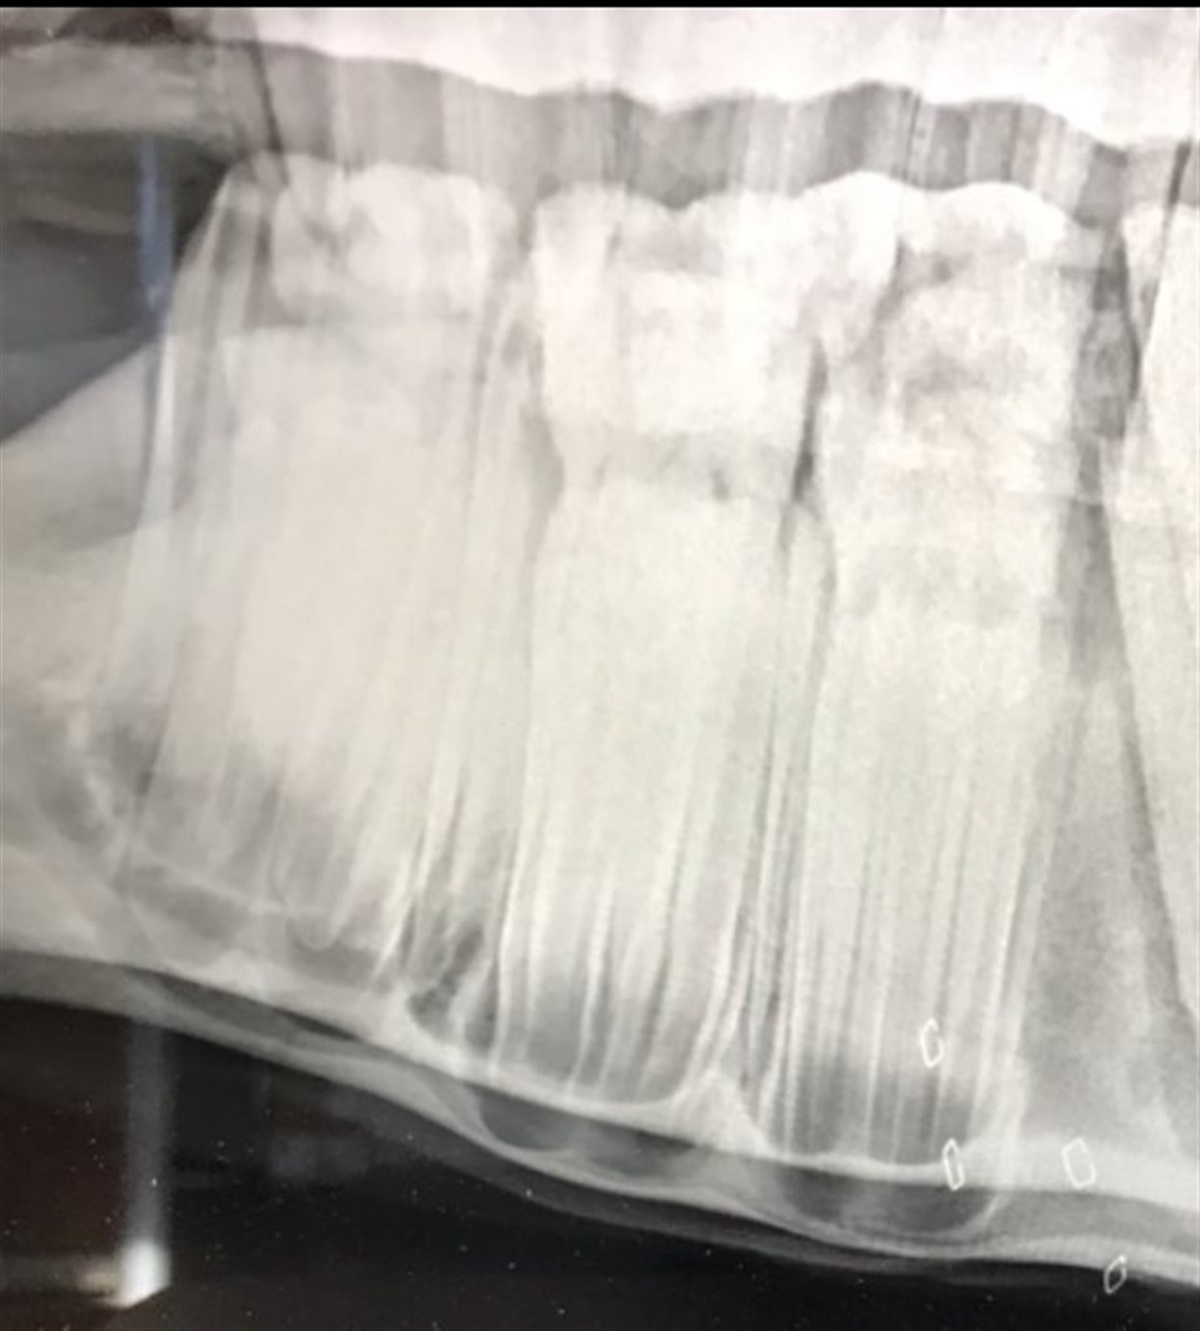

Bulerne skyldes de nye kindtænder, som er ved at blive dannet inde i kæben. Tandrødderne sidder så langt nede (se røngtenbilledet nedenfor) og fylder så meget, at de "skubber" kæbeknoglen ud og derved dannes der buler.